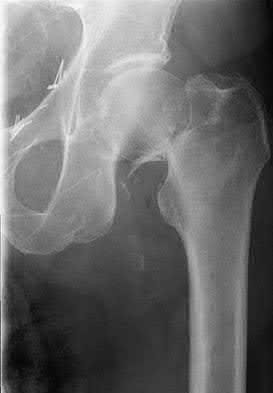

2. # A 35-year-old woman is involved in a head-on collision while driving. Initial radiographs are shown in Figures 8a and 8b. Injury to what vessel increases the risk for osteonecrosis of the injured bone?

1. Dorsalis pedis artery

2. Perforating peroneal artery

3. Lateral tarsal artery

4. Artery of the tarsal canal

5. Artery of the tarsal sinus Corrent answer: 4

The patient has a Hawkins type III talar neck fracture-dislocation with a risk of osteonecrosis ranging from 69% to 100%. Anatomic studies have shown that the artery of the tarsal canal supplies the lateral two thirds of the talar body.

The other vessels listed provide no significant contribution to the talus.